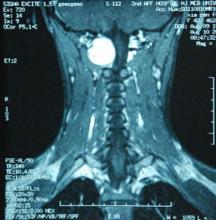

病例:男,19歲,未婚,工人。平時工作成績優異,單位擬提其為幹部,但考核時交白卷自感有愧於領導。病後嗜睡、工作效率下降、發獃。第3天即臥床不起,生活需人料理,整日雙目緊閉,定向不良,記憶減退。不久發展到大小便不能自理,情況日趨惡化。於住院後第12天死亡,屍檢發現為左側顳葉巨大皮樣囊腫,腫瘤源於左側大腦側室內側部分,充滿左側整個側室,左側腦容積擴大。死亡原因系兩側海馬疝形成。

病例:男,52歲,已婚,幹部。10年來反覆發作精神異常而入院。於1980年起失眠,頭昏,情緒低落,休息在家。因既往(1976)胃病手術診斷為原位胃癌,此時也擔心是否患了腦癌,經頭顱CT檢查排除。1981年對妻子外出打牌和女兒交男友不滿,表現易激惹,也一度懷疑妻子、女兒對自己不懷好意,經門診用藥治療緩解。1983年停藥再發,表現同前,經治療好轉。1985年3月曾有輕微發作,表現話多易怒,服藥後很快控制。1986年出現陣發性右面部抽搐右耳聽力下降。1988年又因停藥發病,興奮話多,揮霍無度,到處串門,拜訪已多年不聯繫的師生,為過50歲生日大請賓客,自感聰明,能力強。常規複查頭顱CT,發現右側小腦腦橋角區有一跨中、後顱窩的低密度占位病變,以顱內表皮樣瘤可能性大。經服藥精神症狀又得到控制。1988和1989兩年中出現輕度的病情波動,但大部分時間正常。1991年又發,表現失眠,興奮話多,亂買食品,愛管閒事,不斷訪友,愛提意見,誇耀自己的才能。CT複查片仍可見原有病灶,其形態、部位、大小、密度未見明顯改變。本例屬於情感性障礙與顱內腫瘤伴發,可能後者誘使前者復發的效應。